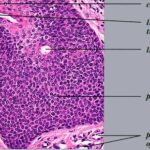

Hidroacanthoma simplex shows sharply demarcated aggregations of cuboid to ovoid cells confined to the epidermis. Eccrine poroma reveals aggregations of uniform basaloid cells that radiate from the basal layer of the epidermis into the dermis . Dermal duct tumor consists of several sharply circumscribed, mainly dermal nodules composed of poroid and cuticular cells. Ductal structures are frequently observed. Poroid hidradenoma is characterized by intradermal, solid, and cystic aggregations of poroid cells.